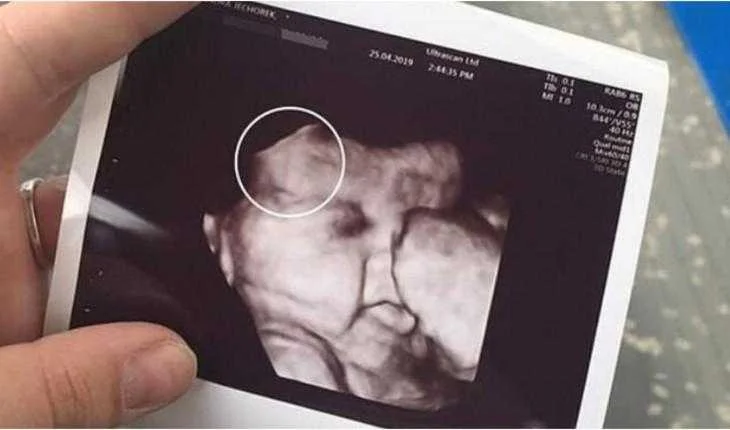

No ultrassom de 34 semanas, era possível conferir perfeitamente que a pequena Maya já tinha um lindo e vasto cabelo antes mesmo de nascer.

Até os médicos e as enfermeiras se surpreenderam, pois contaram que ainda não tinham visto um bebê cabeludo daquele jeito.

“Esperava que ela tivesse cabelo por causa do ultrassom, mas ver aquele bebê com aquele cabelo grosso e preto foi inacreditável “, disse a mãe orgulhosa, contando que tem a madeixa mais escura, por isso acredita que a filha puxou a ela.